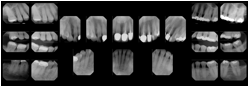

Intra-oral radiography typically involves acquisition of multiple images of various parts of the dentition. Many digital radiographic systems offer customized templates that are used for displaying the images in a study on the screen. These templates may also be referred to as mounts or view sets. The Structured Display Object represents a standard method of encoding and exchanging the layout and intended display of Structured Displays. A structured display object created in this manner could be stored with a study and exchanged with images to allow for complete reproduction of the original exam.

1. A patient visits a General Dentist where a Full Mouth Series Exam with 18 images is acquired. The dentist observes severe bone loss and refers the patient to a Periodontist. The 18 images from the Full Mouth Series along with a Structured Display are copied to a DICOM Interchange CD and sent with the patient to see the specialist. The Periodontist uses the CD to open the exam in his Dental Radiographic Software and consults via phone with the General Dentist. Both are able to observe the same exam showing the images on each user's display using the exact same layout.

In most standard cases, images are oriented in structured layouts. These structured displays are useful to be shared between providers for reference purposes.